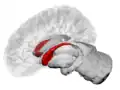

Caudate nucleus highlighted in green on coronal T1 MRI images

Caudate nucleus highlighted in green on sagittal T1 MRI images

Caudate nucleus highlighted in green on transversal T1 MRI images